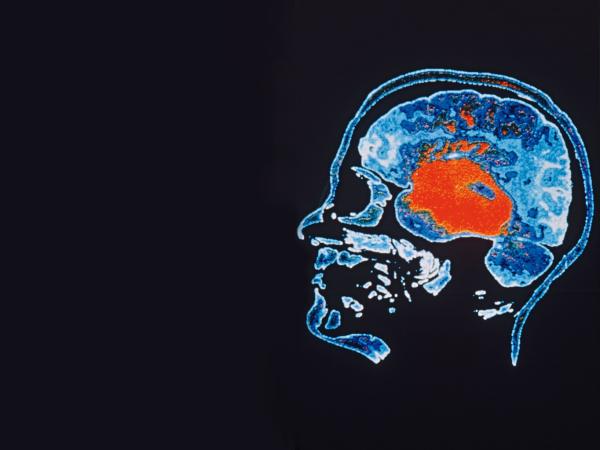

Coraz precyzyjniejsze analizy połączeń między neuronami mają wyjaśnić, jak powstają myśli i pamięć, umożliwić skuteczne leczenie zaburzeń psychicznych.

Ludzki mózg opisują astronomiczne liczby. Składa się on z ok. 100 mld neuronów (komórek nerwowych), a jeden neuron tworzy średnio kilka tysięcy połączeń z innymi komórkami nerwowymi. Każdy z nas nosi więc w głowie niewyobrażalnie skomplikowaną sieć złożoną z ok. 100 bln (czyli stu tysięcy miliardów) połączeń.

Minione dwie dekady to nieustający postęp w podglądaniu na żywo pracy mózgu. Czy przybliżyły nas one do odpowiedzi na kluczowe pytanie: jak ten organ naprawdę funkcjonuje?